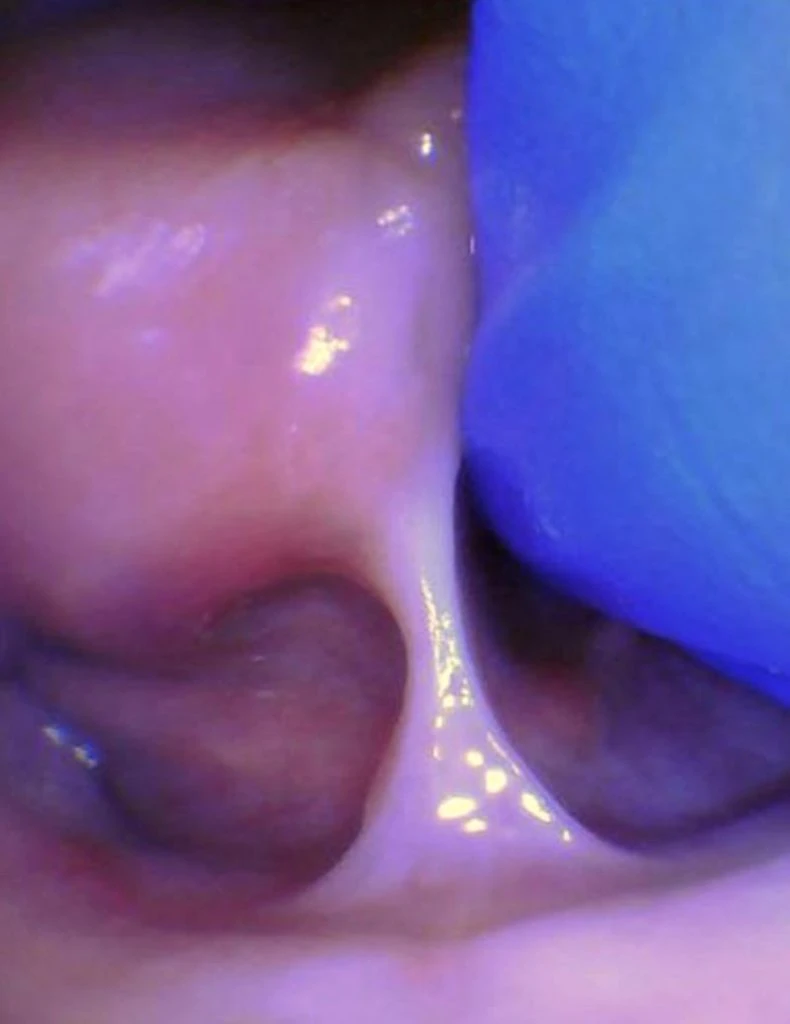

These images show the spectrum of posterior tongue restriction in an infant.

View posterior tongue restrictions